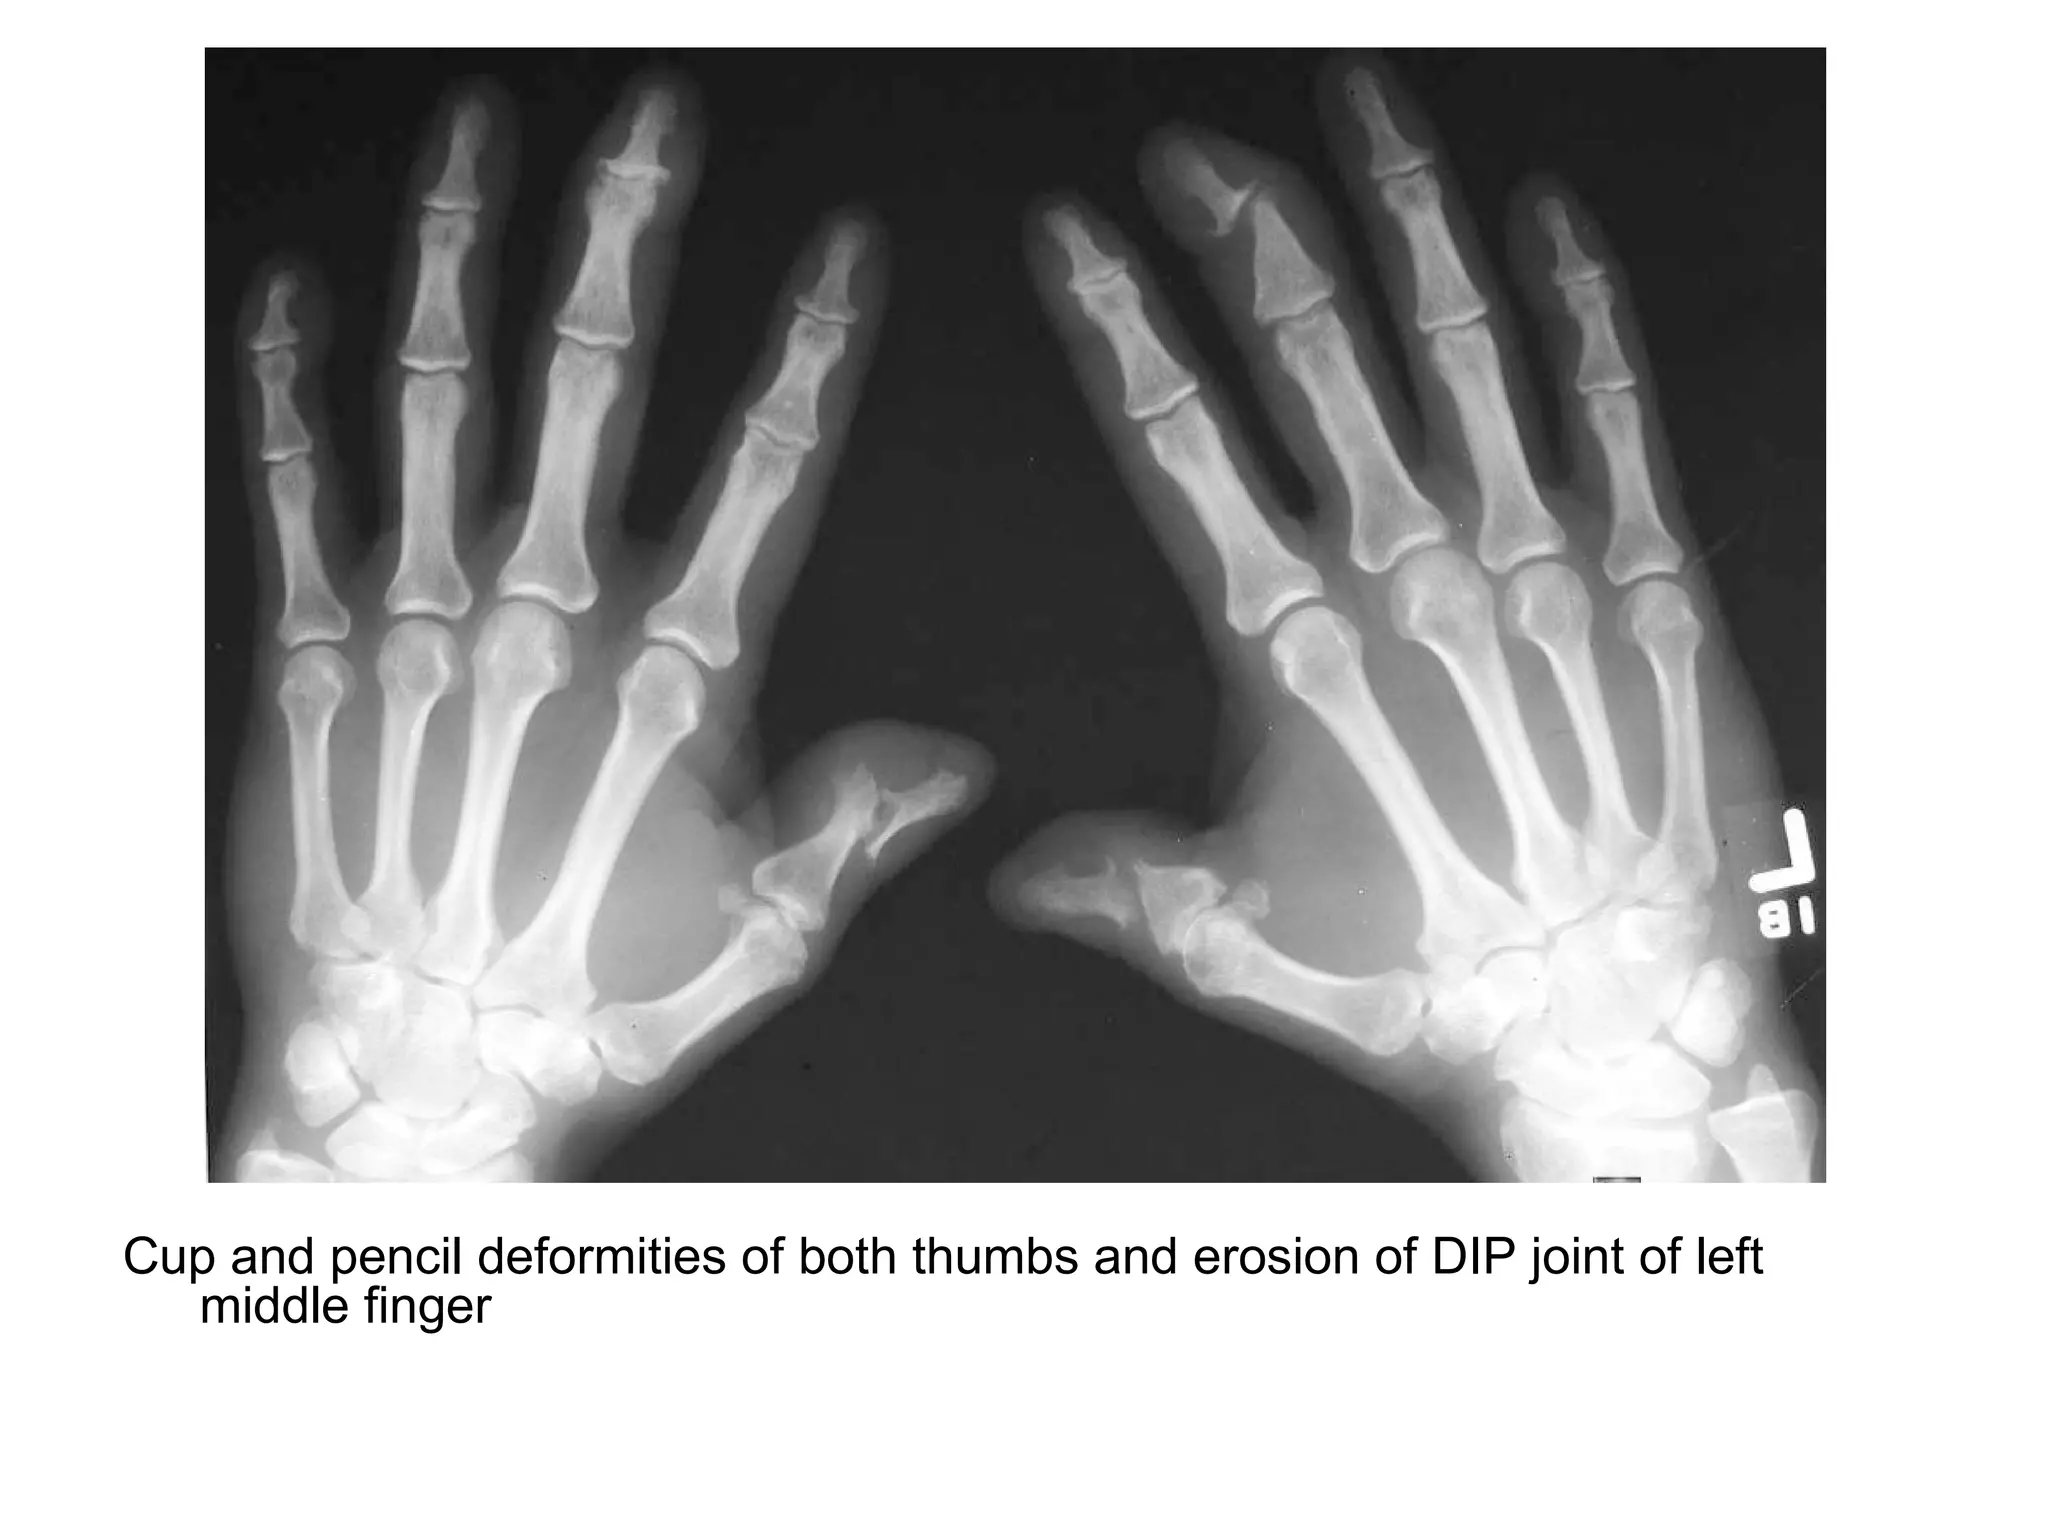

Cup and pencil deformities of both thumbs and erosion of DIP joint of left

middle finger